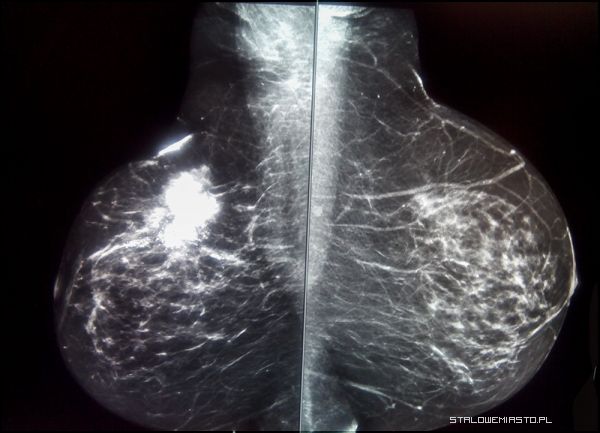

Mammografia spektralna

To mammografia podobna do tej najczęściej spotykanej, z tą różnicą, że pacjentce podawany jest dożylnie kontrast. Tego typu badania wykonuje się celem oceny stopnia zaawansowania już stwierdzonego nowotworu lub po powstałych przy tradycyjnym badaniu wątpliwościach dotyczących zachodzących zmian.

- Podając kontrast robimy to dwoma energiami: wysoką i niską. Zmiany nowotworowe mają tzw. neoangiogenezę, czyli nowotworzenie naczyń. Ilość naczyń stworzonych w guzie nowotworowym jest większa i silniejsza. Dzięki dwuenergetyce aparat składa te obrazki i pokazuje nam konkretne miejsce, które podejrzewamy. Jeśli uległo wysyceniu, rzeczywiście jest to nowotwór- mówi lek. Krzysztof Antonowicz.

Dzięki temu badaniu można zdiagnozować w piersi wszystkie zmiany.